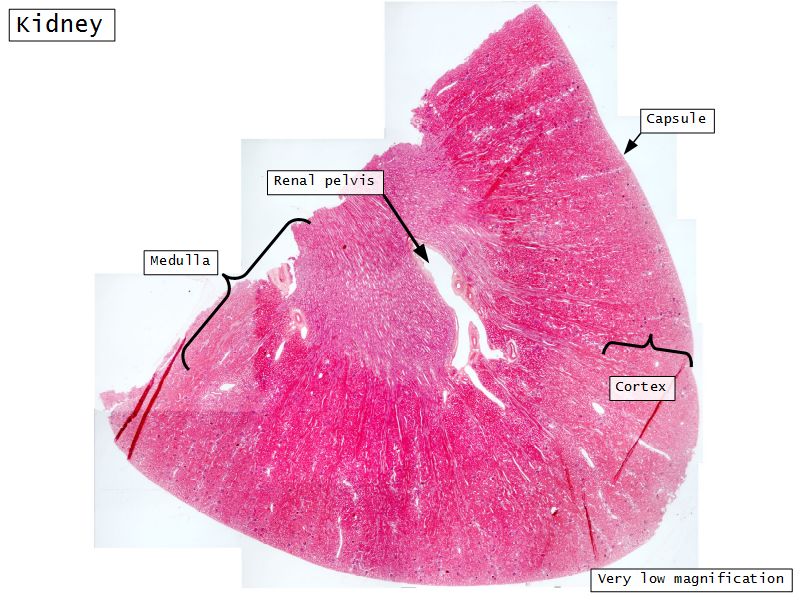

Kidney

- Capsule

- Cortex

- Medulla

- Multilobar

Multilobar

- Conical mass (pyramid)

- Medullary tissue

- capped with

- Cortex

- Delineated by

- Renal columns

- Apex of pyramid

- Papilla

- Projects into renal pelvis

- Make an annotated drawing of the macroscopic view of the kidney.